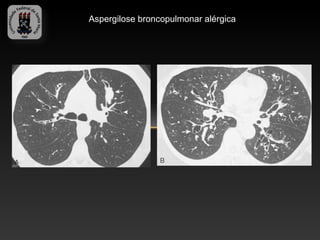

-Aspergilose broncopulmonar alérgica

-   Asma, eosinofilia sanguinea, infiltrados pulmonares e alergia aos

antígenos do Aspergillus.

-   Chiado, dispnéia, tosse produtiva e plug de catarro.

-   TC: Impactação mucoide no brônquio (opacidade linear ou

ramificada), vias aéreas lesadas e bronquiectasias.

Aspergilose broncopulmonar alérgica